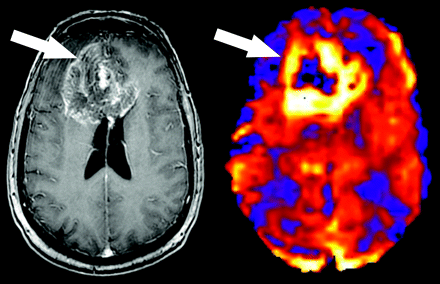

A 57-year-old woman with atypical meningioma. An avidly enhancing falcine-based mass is demonstrated on the postgadolinium image (left). ASL map demonstrates ringlike hyperperfusion corresponding to the outer margins of the tumor (right, arrow).